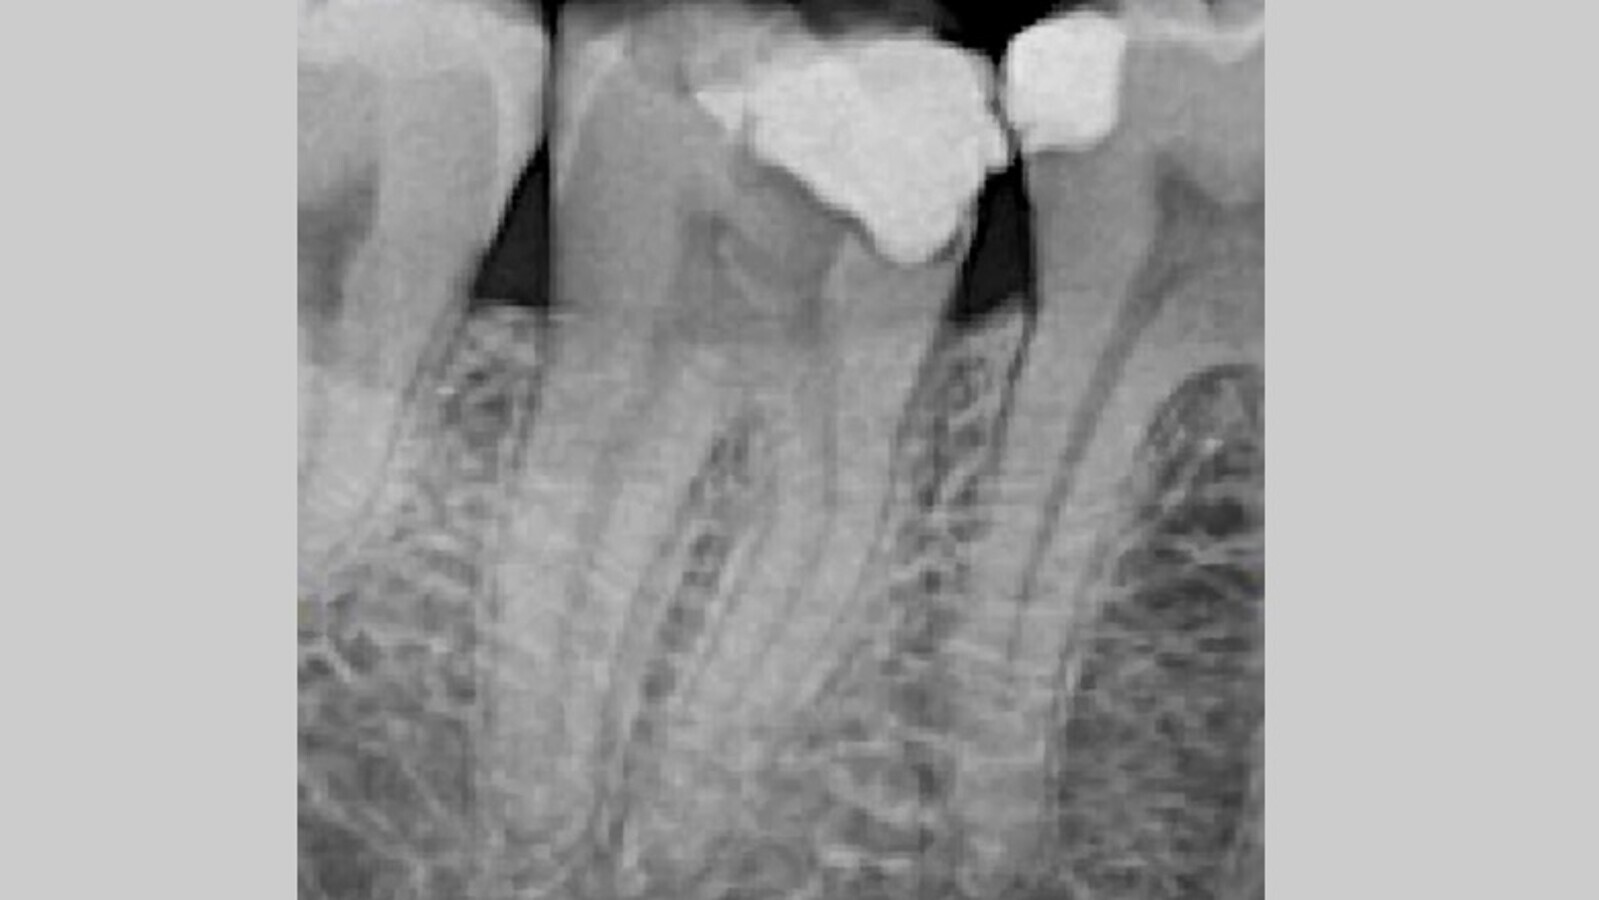

Una vez conformado e irrigado el sistema de conductos, se realiza la selección del material de obturación. En este caso se calibran 3 conos Autofit 04 (SybronEndo greater taper) y se comprueba la adaptación mediante una radiografía de conometría (Fig. 4).

Fig. 4. Radiografía periapical de conometría.

Una vez confirmada la perfecta adaptación del material de obturación, se introducen los conos calibrados recubiertos en una fina película de cemento resinoso AHPLUS (Dentsply, Sirona) y escogemos una técnica termoplástica como técnica de obturación, concretamente con el uso de termocompactadores (Fig. 5).

Fig. 5. Radiografía periapical final de la endodoncia del 4.7.